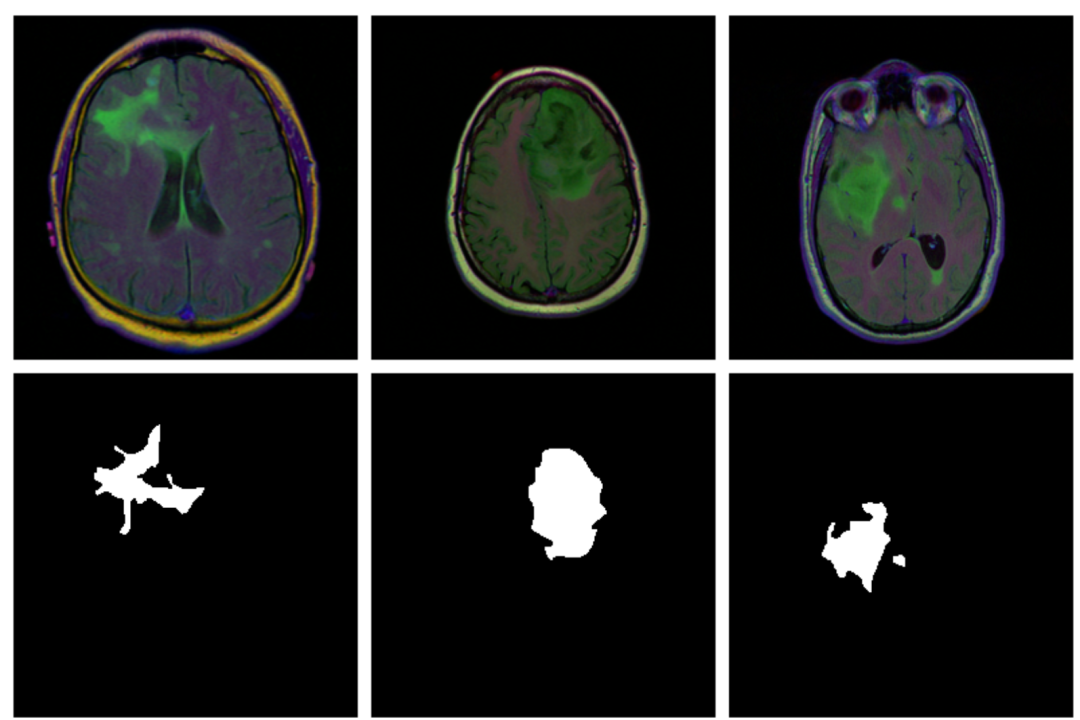

本示例演示检测脑部扫描中的异常,使用的数据集包含 MRI 图像以及手动创建的 FLAIR 异常分割掩码。即对于每位患者,多个位置都进行了切片,每位患者的切片数量不同。

图:不同样本的脑影像(上图)以及掩码(下图)。大多数切片没有显示任何病变,相应的掩码到处都是黑色,而有病变的掩码位置标记为白色,模型的任务便是预测任意输入样本的掩码(即病变位置)。